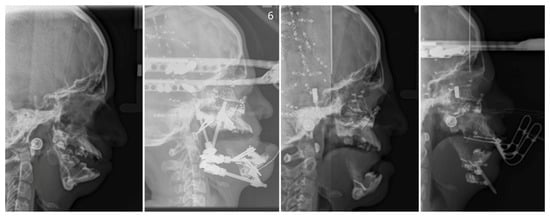

- Age 13 to 18—orthognathic therapies, maxillomandibular and nasal reconstruction as well as integration into society. Multistage reconstructive treatment forming face is possible in this age and makes noticeable improvements (Figure 6). However, if possible, it is recommended to start therapy at an earlier age. The sooner therapy begins gives the higher possibility of achieving optimal results (Figure 7).